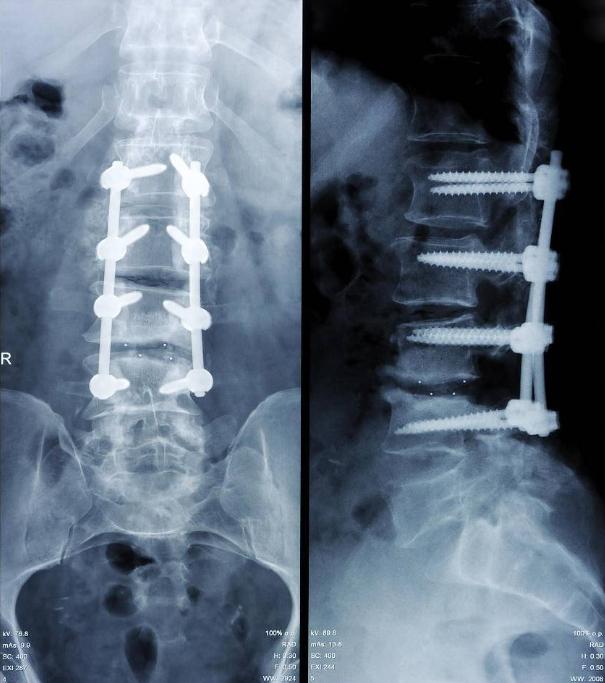

手术治疗过后的X光片,可以看到钢钉

颈椎手术的历史已经有几十年了,在我国也有三十多年的历史,手术量也不断增加,医生的技艺的精准度也增加了,手术的风险性却不断减低,并发症发生率非常小。